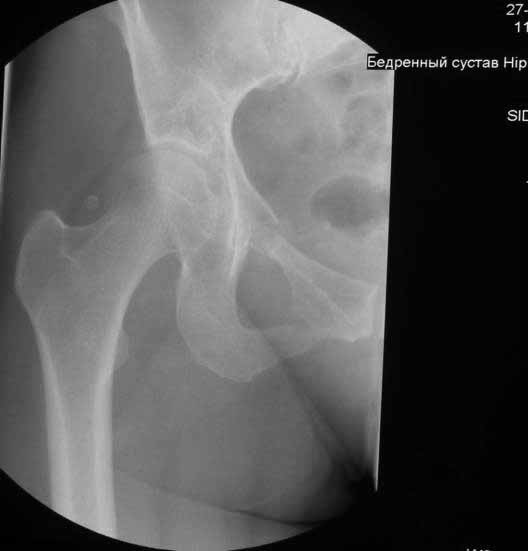

Уважаемые коллеги. Хотелось бы услышать мнения и советы по представляемому случаю.

Пациентка 45 лет. Бесцементное эндопротезирование левого тазобедренного сустава 6 лет

назад (впадина RM, Mathys, металл-металл, ножка Зульцеровская). За 10 лет до

протезирования коррегирующая остеотомия бедренной кости, которая не срослась в течение

года до удаления пластины, а затем срослась в течение 3 месяцев иммобилизации в кокситной

повязке. После протезирования получилось наблюдать пациентку почти постоянно, поскольку

через 2 года синтезировал ей лодыжки на оперированной стороне, затем, через несколько

месяцев удалил фиксаторы, а в 2009г. резецировал мениск на противоположной стороне. Боли

все эти годы не беспокоили. Пациентка чуть выше среднего роста, вес тела нормальный.

Физические нагрузки переносила хорошо. Работает на 7 этаже без лифта. Год назад экстирпация

матки по поводу лейомиомы больших размеров. Несколько месяцев назад появились боли в

области левого тазобедренного сустава. При рентгеновском и КТ исследованиях (июль с.г.)

нестабильность тазового компонента. От предложенной замены протеза пациентка на тот

-Если думать о ревизии, то когда? На представленных снимках тазобедренный сустав до и

сразу после операции, затем 2 снимка 2009г., когда ничего не беспокоило, затем КТ 2-х

месячной давности и вчерашние рентгенограммы обоих тазобедренных суставов.